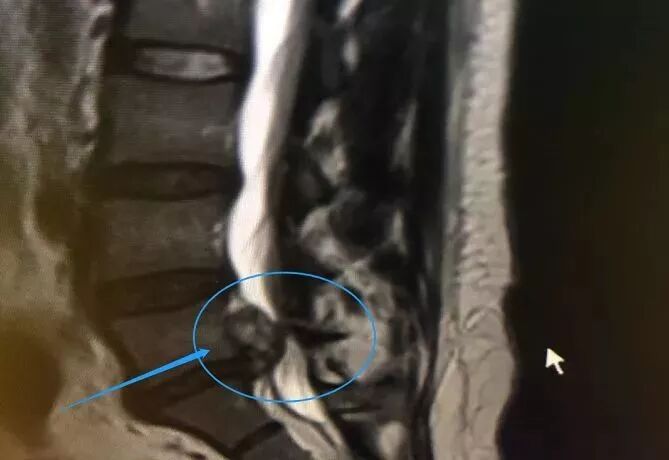

而导致张女士脚不会动的

主要原因是腰间盘突出压迫神经

导致的足下垂